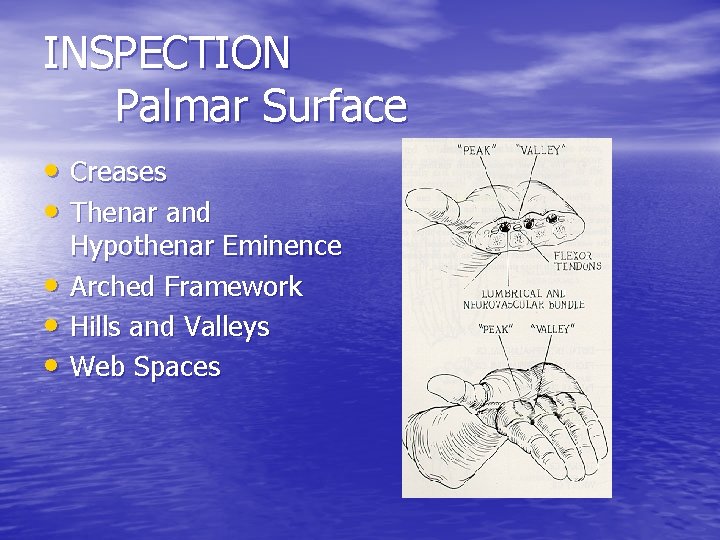

INSPECTION Palmar Surface • Creases • Thenar and • • • Hypothenar Eminence Arched Framework Hills and Valleys Web Spaces